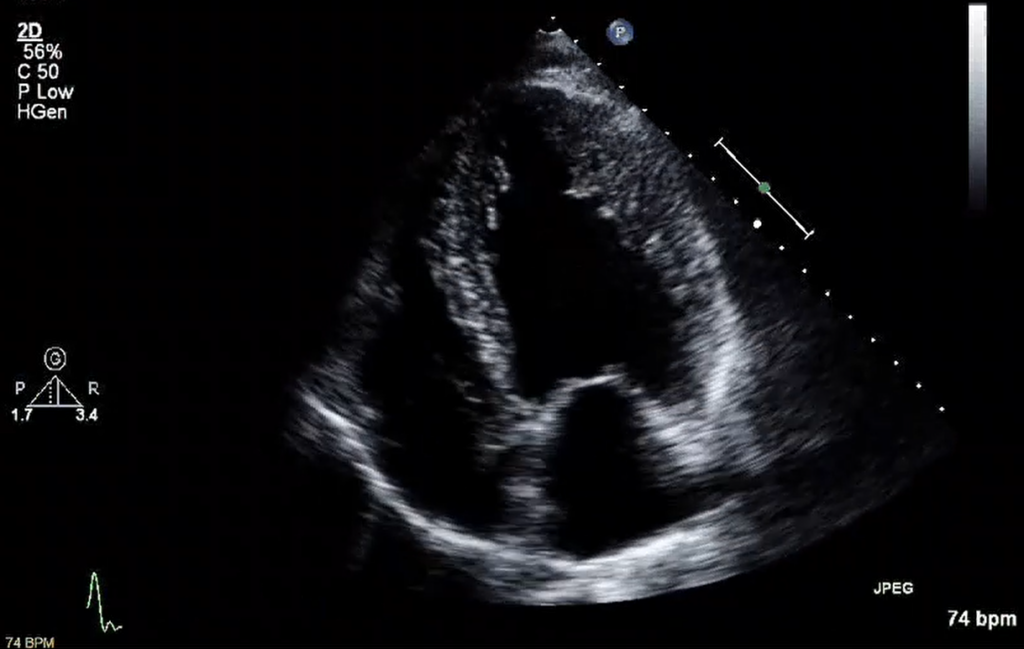

心エコー(心臓超音波検査)とは

心エコーは、超音波を使って心臓の形や動き、弁の状態、血液の流れを調べる検査です。胸にゼリーを塗り、プローブ(超音波を出す機器)を当てて観察します。通常の検査は20分程度で行われることが多く、放射線を使わないため被ばくの心配がありません。

弁膜症の評価では、心エコー検査が最も基本的かつ中心的な検査となることが多いです。 心エコー検査では心臓の形やサイズに加えて、血液の流れる方向を色で表示する(カラードップラー)ことができ、狭窄や逆流している血液の流れを視覚的に捉えることができます。